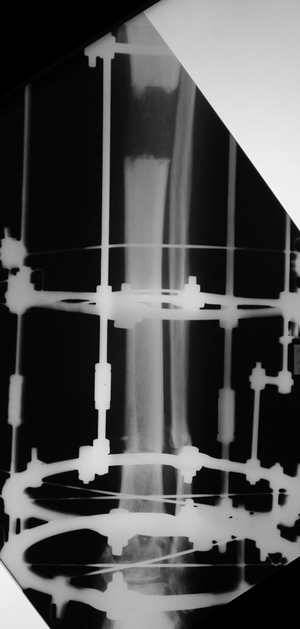

Адаптация отломков гексаподом за 5 дней (рис 5). Замена гексапода на обычные штанги (рис 6 и 7)